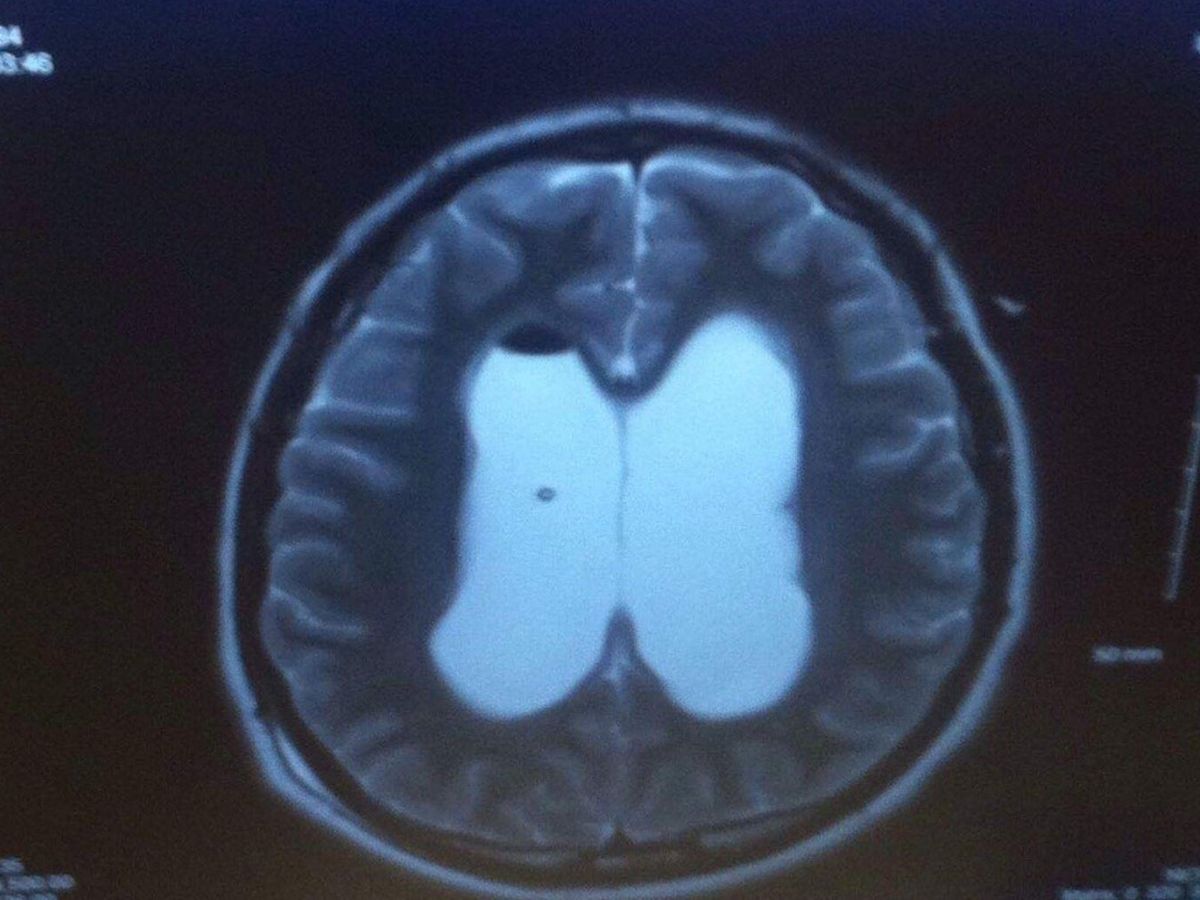

Hi, im trevor, im 23 and i have a brain tumor that is inoperable and type 1 diabetes. Im not normally one to ask for help, but Medicaid cant cover everything for me, the funds will go twords medical issues i still have, and living expenses, as i dont have a job and i cant drive, i tryed to apply for ssi but ive been denied, thats why im asking. My sister told me to make this as a way to helping me out.